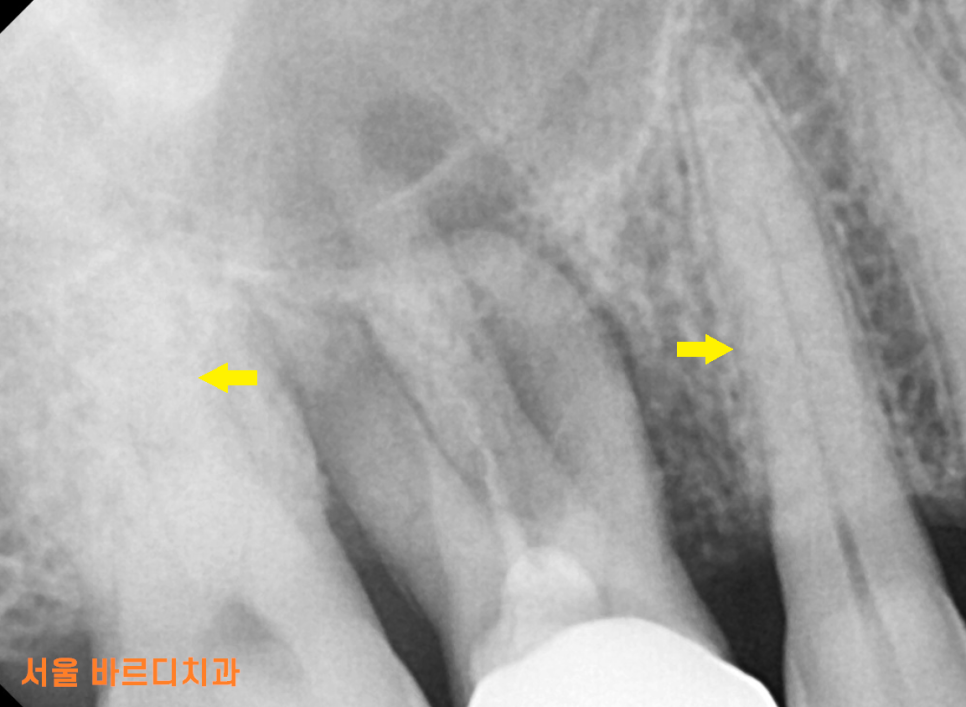

잇몸뼈가 남아있는 양 옆 치아와 비교해보아도

유독 문제 치아 주변으로만 까만 것이 보이실겁니다.

뼈가 다 녹아서 그렇습니다.

x-ray 상에서 뼈가 너무 많이 녹아있어

임플란트.. 바로는 어렵겠다... 감이 왔습니다.